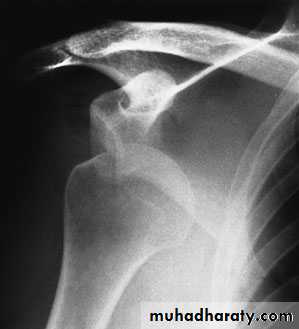

X-ray:

anteroposterior,cephalic tilt and are advisable.

axillary views

a stress view is sometimes helpful in distinguishing between a Type II and Type III injury: